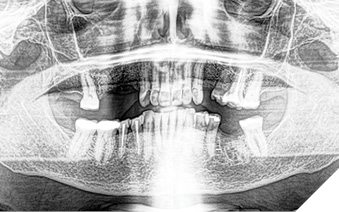

A 65-year-old woman comes to the office with the chief complaint of worn-down teeth, missing teeth, tooth sensitivity, especially on maxillary teeth and TMJ pain. Her past medical history was reviewed and was significant for asthma, insomnia, hypercholesterolemia, hypothyroidism, and anxiety disorder. She denied any sleep disturbances. Her medications included salbutamol, ezetimibe, quetiapine, and levothyroxine. She referred to being allergic to dust and shellfish and sensitive to propofol. She had a right mastectomy in 2014 due to breast cancer. No chemotherapy or radiation was done. Her diet was considered normal, and she denied any consumption of acidic drinks and denied any history of regurgitation. She denied any parafunctional habits during the day. She was using a maxillary transitional partial denture since she had lost some of her teeth due to fracture and caries. No other problems were evidenced. Intraoral exam showed moderate attrition lesions of posterior teeth, porcelain fused to metal crowns on teeth 46 and 47 had the porcelain portion worn down, exposing the metal substructure. Missing teeth included teeth 14,15,16,18,24,28, 36,38,48. Palatal surfaces of maxillary anterior teeth also appeared worn down. An abfraction lesion was found on tooth 23. No carious lesions were found in any of her teeth. Composite restorations on mandibular anterior teeth were chipped or were missing (Figs. 6-11) She also presented with limited mouth opening: 35 mm interincisal distance at maximum opening. There was bilateral pain on palpation of preauricular areas. Her pain was the worst early in the morning which suggested night parafunction. No crepitus, or joint clicking were found.

Fig. 6

Fig. 7

Fig. 8

Fig. 9

Fig. 10

Fig. 11

Articulated diagnostic casts showed very limited to no overjet and 90% of overbite. The wear pattern on the palatal aspect of her maxillary teeth appeared to be secondary to her tight occlusion since mandibular anterior teeth were in close contact with these surfaces with no “room” for protrusive movements. The diagnosis for this patient was: partial edentulism, failing existing restorations and attrition and abfraction secondary to parafunction. We discussed different options, including orthodontics in order to increase her overjet so we could have prosthetic space to restore her worn down teeth. We also discussed tooth replacement options. After a second consultation appointment which she attended with her husband, she decided that she did not want to replace her teeth with removable prosthetics. She also declined referral to an orthodontist. After discussion of multiple options of treatment to address all her chief complaints, her treatment consisted of a full mouth reconstruction with full coverage restorations in Zirconia for teeth 11-13,17,22-23,25-27,32-42, 44-47 and partial coverage restorations with lithium disilicate restoration for teeth 33,34 and 43. Replacement of teeth was achieved with a fixed partial denture to replace tooth 36 and a 3-unit implant supported bridge to replace teeth 24-26. In terms of occlusion, we created a more favorable occlusion with a proper anterior guidance, canine disclusion with more freedom for protrusive movements, which hopefully would decrease the parafunction, and alleviate some of her muscle pain. Before completing the case, the patient spent several weeks with provisional restorations which reflected the increase in vertical dimension of occlusion and the new occlusal scheme. During this trial phase, we assessed comfort, esthetics, function, decrease in pain and speech (Figs. 12-17).